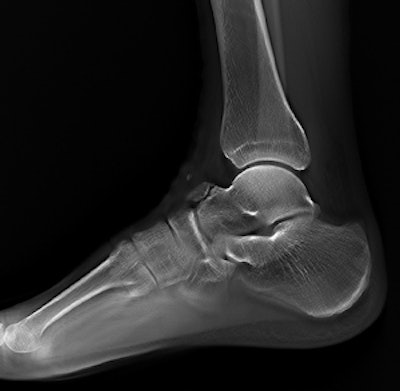

Tomosynthesis image of an ankle taken with Shimadzu's RADspeed Pro digital radiography system.The emphasis of Philips' researchers has been on developing technologies for improving diagnostic quality while eliminating inefficiencies when using mobile digital radiography systems at the patient's bedside. The new SkyFlow scatter correction algorithm reduces the effect of scattered radiation for nongrid bedside chest exams, allowing the operator to obtain DR images with grid-like contrast, but avoiding the time and effort involved in attaching and detaching a grid.